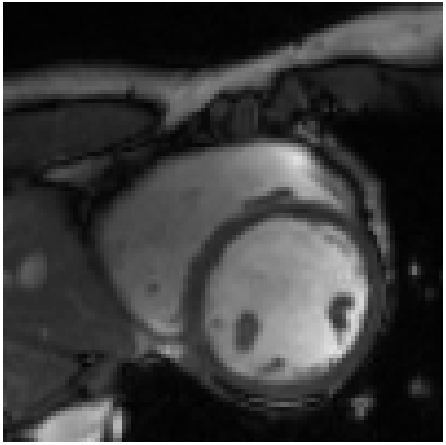

Refer to caption

(a)

(b)

(c)

Figure 4: Qualitative evaluation of reconstruction performance of our method on cardiac cine MRI (ACDC dataset). (a) Original cardiac MRI scan; (b) Its reconstruction and (c) Differences between original (minuend) and corresponding reconstructed (subtrahend) slice. Note that to reconstruct a slice xnsubscript𝑥𝑛x_{n} the mixing coefficient α𝛼\alpha in Equation 1 is set to zero. Blue corresponds to negative and red to positive differences. Image intensities are scaled to a [0,1]01[0,1] range. All difference images use the same color scale [1,1]11[-1,1].